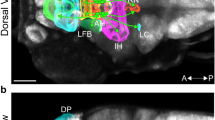

Immunostaining for HIF-1α and TH during maturation of the rat carotid body, i.e. at E20, birth (P0), and P2, P7, and P14 (A) and after hypoxia in vivo (P40) (B). In the overlaid images, cells that are only positive for HIF-1α appear red, TH-positive (TH+) cells appear green, and cells expressing both of these markers appear yellow. In early stages of development (i.e. E20, P0, and P7; n = 5 or 6), HIF-1α is expressed by both TH+ and TH− cells. At later stages (P7 and P14; n = 5 or 6), staining for HIF-1α and TH is present in different cells. (B) This graph depicts the ratio of HIF-1 staining (as quantified by densitometry) in TH+ vs TH− cells. At early stages (E20, P0, and P2; n = 5 or 6), HIF-1α staining in TH+ and TH− cells is of the same intensity; whereas at later stages [P7, P14, and P40 normoxic (NX) rats; n = 5 or 6], HIF-1α is expressed primarily in the TH− cells. After exposure of P40 rats (n = 5) to hypoxia (HX) in vivo, expression of HIF-1α was strongly enhanced in TH+ cells. *Statistically significant difference compared with the ratio at E20. †Statistically significant difference compared with P40 rats exposed to normoxic conditions.

Immunoreactivity toward HIF-2α was present and of similar intensity in CB of all ages and was restricted to cells arranged in clusters. Double immunostaining (HIF-2α/TH) revealed that this protein was expressed in glomus cells (TH+) only and not in sustentacular cells (TH−) (Fig. 4). Indeed, all cells expressing HIF-2α also expressed TH.